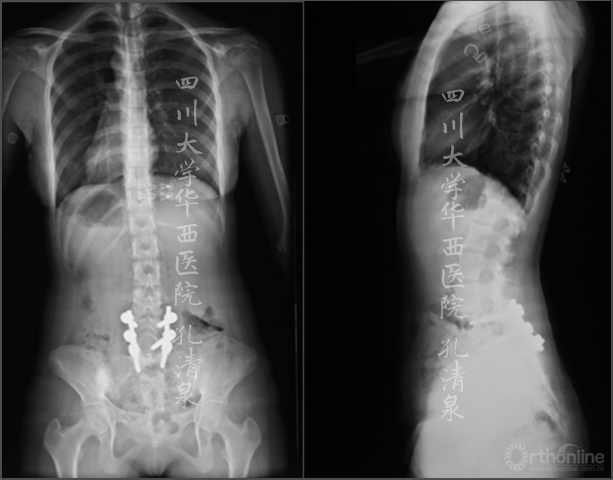

治疗:经后路腰4-骶1固定、腰5滑脱复位、椎管减压、植骨融合术,术后患者左腿疼痛消失,术后复查侧凸残留17°,术后6月复查发现侧凸自发的减轻,术后两年复查时侧凸得到完全的矫正。

图4 术后复查 侧凸残留17°

图5 术后矢状面CT重建显示复位情况良好

图6 术后三月复查侧凸

图7a 术后五年复查X线无侧凸,无骨盆倾斜,胸椎后凸、腰椎前凸序列良好